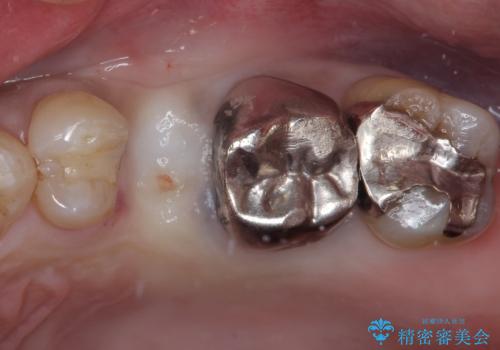

- 頻繁に銀歯が外れてしまうとのことで来院された患者様です。

歯肉の中、深いところまでむし歯が進行しており、歯根を部分矯正で引っ張り出してから補綴治療を行うか、抜歯してインプラント補綴治療を行うか選択することになりました。

海外での勤務があり、部分矯正は困難とのことで、インプラントによる補綴治療を行うこととしました。